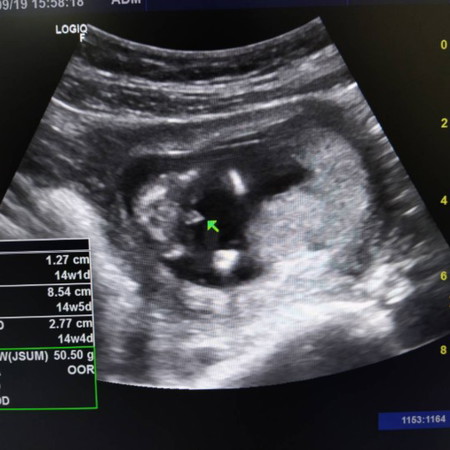

14สัปดาห์1วัน หมอบอกเพศชายจ้าแม่ๆว่าใช่มั้ยคะ

ชัดเลยค่ะแม่ เพศชายค่ะ ยินดีด้วยนะคะ

ยินดีด้วยค่ะแม่ๆ ได้เพศชายแน่นอนค่ะ

จู๋น้อยมาแล้วคุณแม่💓💓💓

จู๋โผล่เลยค่ะชาย100% 555